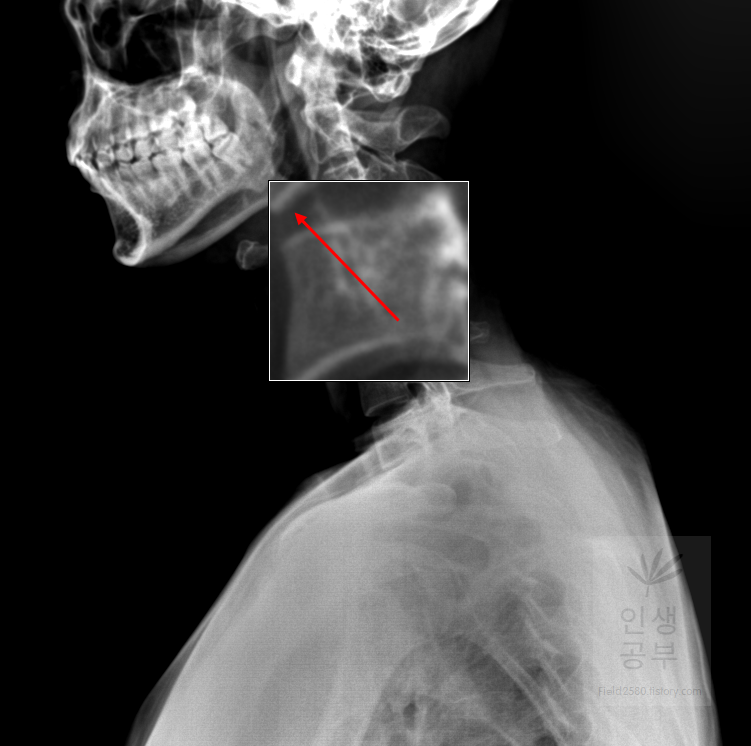

돋보기 화면에 ±가 있는 버튼을 이용해서 화면 전체의 크기를 조절할 수 있는 반면에 부분적인 부분만 확대할 수 있는 방법이 있습니다. 바로 매직 글래스메뉴를 이용해서 부분적인 확대 버튼을 이용하실 수 있습니다. 또한 부분적인 확대 화면 안에서도 추가적인 확대와 축소를 이용할 수 있습니다.

X-ray화면 창에서 마우스 오른쪽 버튼을 클릭해 줍니다. 그 후에 매직 글래스라고 적힌 항목을 선택해줍니다.

부분적으로 확대해서 보고 싶은 X-ray화면에 마우스 왼쪽을 클릭해서 확대해줍니다. 부분적으로 네모칸이 생기면서 선택한 부분을 조금더 크게 보여주는 창이 생깁니다.

만약에 조금 더 크게 보고 싶다면 마우스 왼쪽을 누른 상태에서 Ctrl을 누른 후에 11시 방향이나 12시 혹은 1시 방향으로 올려주면 매직 글래스 화면 내에 부분적으로 확대된 X-ray 화면이 더 커집니다.

다시 축소하고 싶다면 마우스 왼쪽을 누른 상태에서 Ctrl을 누른 후에 4시 6시 혹은 8시 방향으로 내려주면 매직 글래스 안에서 부분적으로 확대된 X-ray 화면을 줄일 수 있습니다.